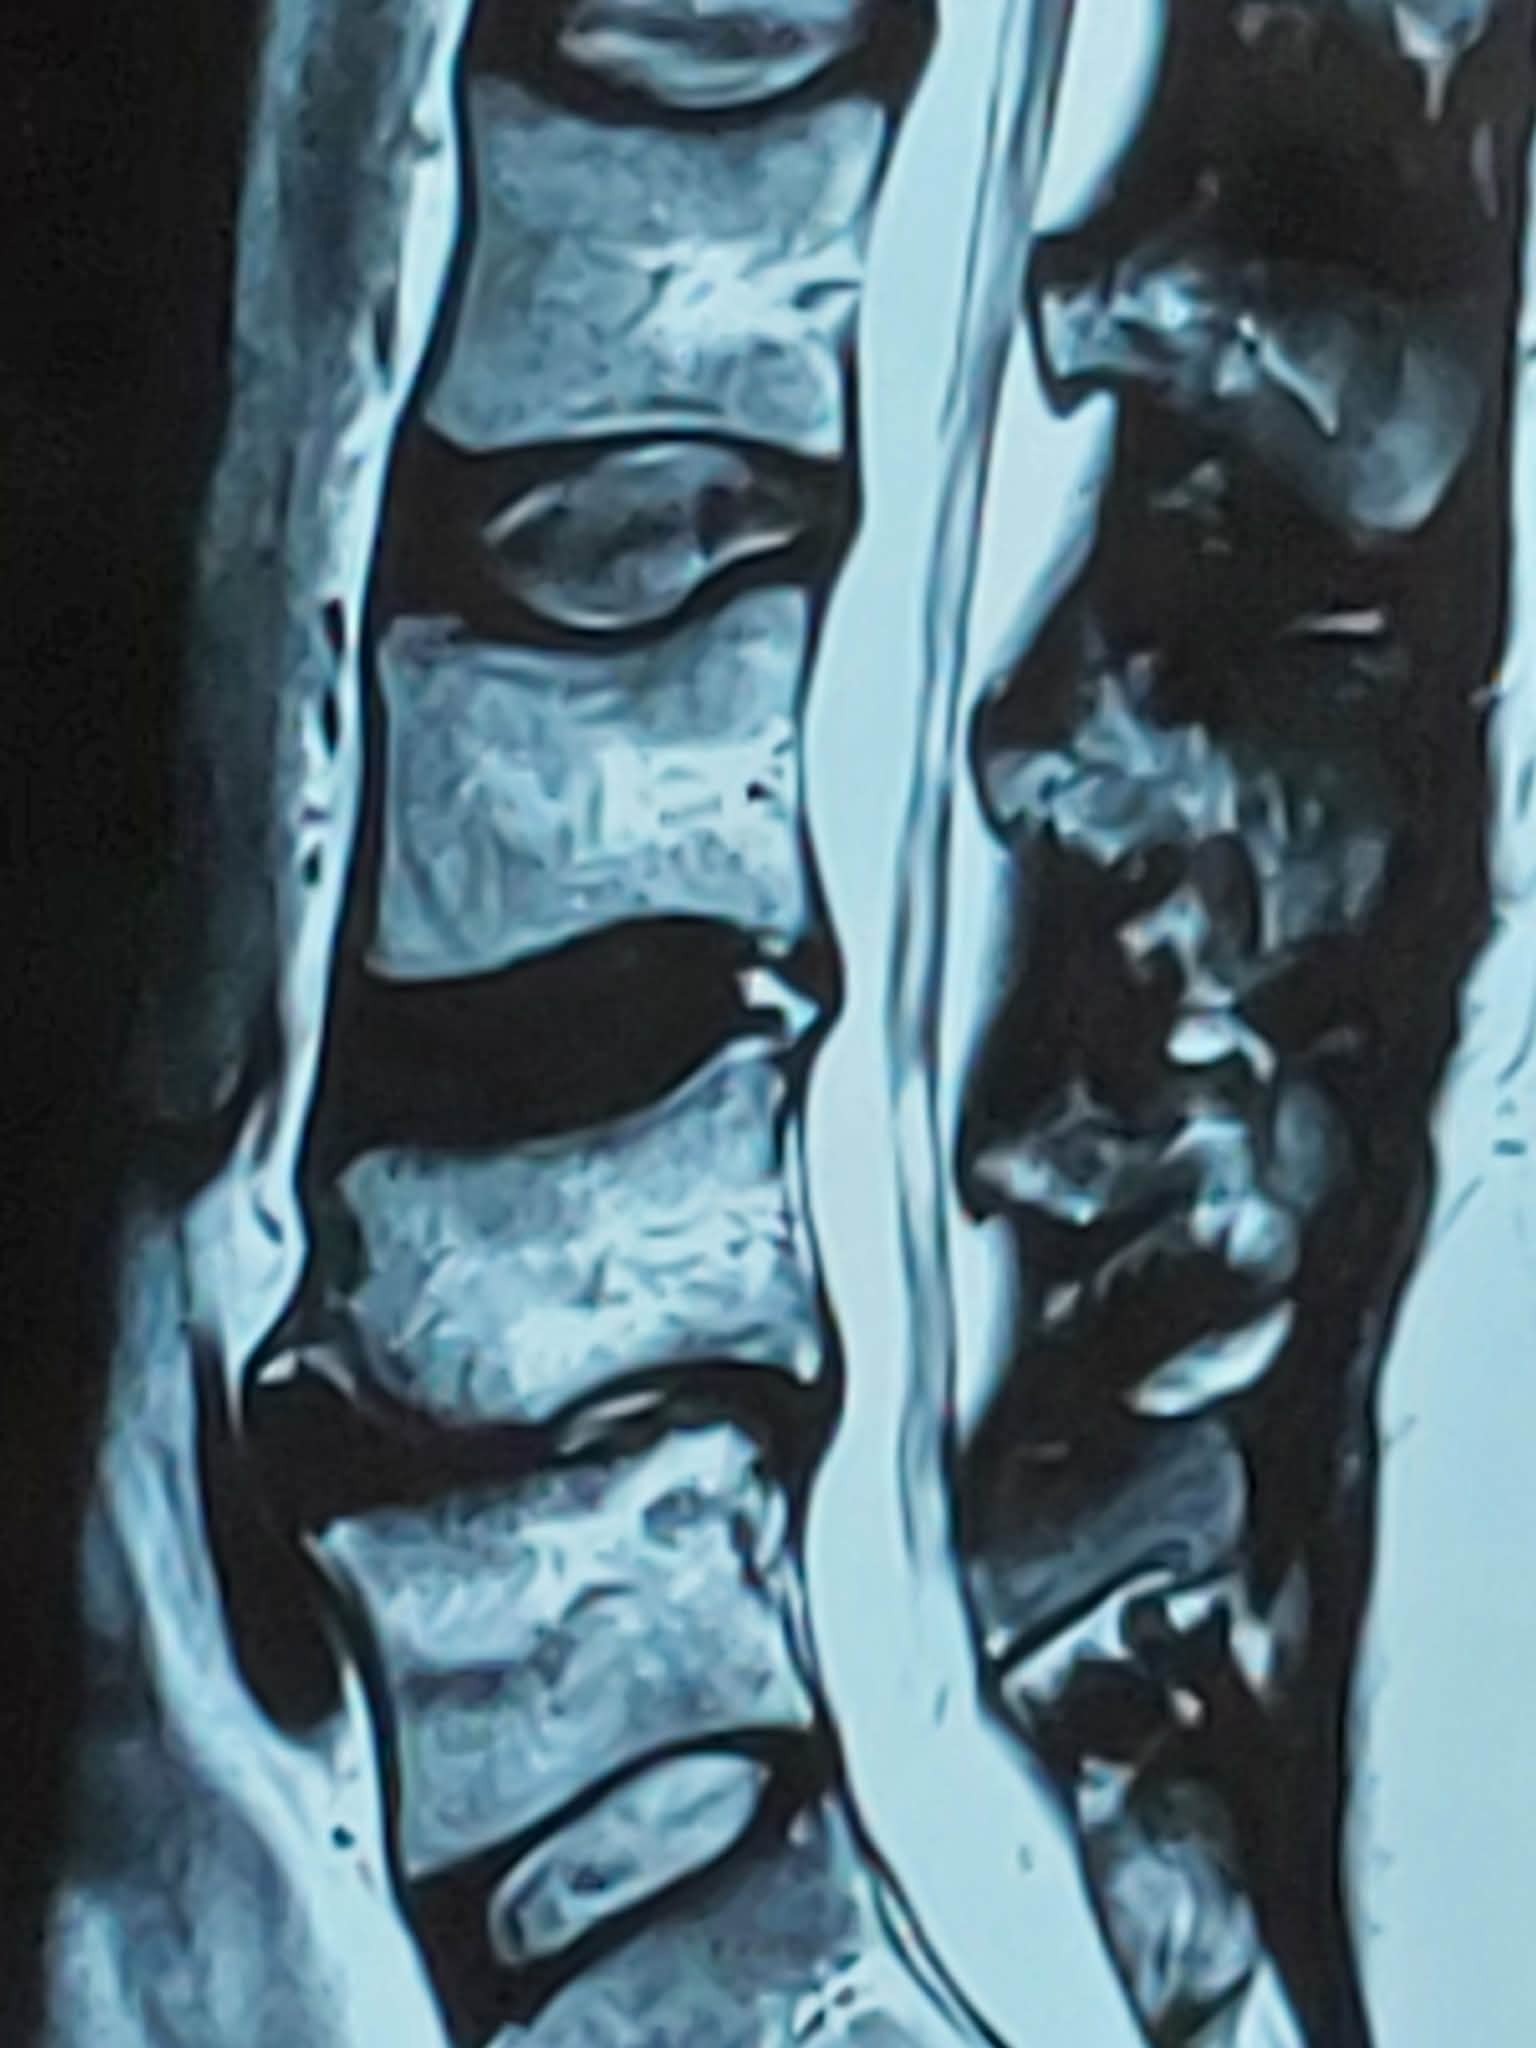

Tanner has been facing some very serious health concerns and recently discovered he needs not 1, but 2 surgies. One is a major procedure to fix his part of back. This is where he really needs support.

This past Oct. I again urged he get another look. That has resulted in Tanner discovering he has no disc between two of his vertebrae in his lower back. It is bone on bone. Tanner does not have pto...sick time...fsa...none of that with his current line of work. As of right now he doesn't even have a place to live. We have been broken up for 6 months....I have agreed to help him through this. He's had to replace his vehicle twice this year...both times wear and tare repairs that would have been more than the cars were worth...so he has no savings left.